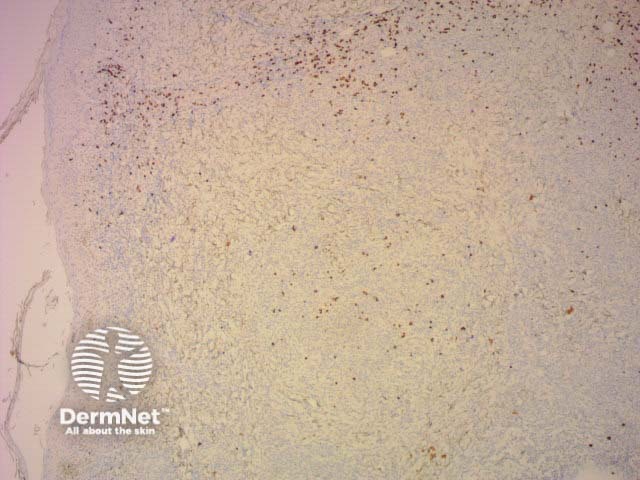

CD3 |

T-cell marker; strongly positive in mycosis fungoides |

CD3